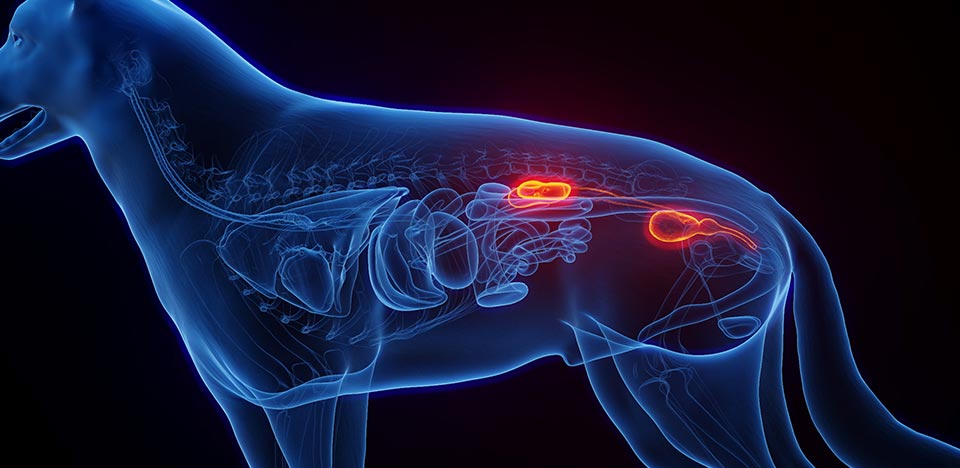

경기동물의료원 투석센터는 급성신장손상, 만성콩팥병의 급성기 손상 등 심각한 신장질환을 앓는 반려동물을 위해 신장기능을 보조하거나 대체하는 고난도 치료인 혈액투석/복막투석을 전문적으로 시행하는 센터입니다. 고가의 전용 투석 장비와 생리학.약리학적 감시 체계, 전문 의료진의 집중 치료를 통해 신장의 급성기 손상 환자의 회복을 도모하는 희망의 공간입니다.

혈액투석은 몸속에 쌓인 노폐물과 과도한 수분을 제거해 아이의 소중한 생명을 지키는 치료입니다.